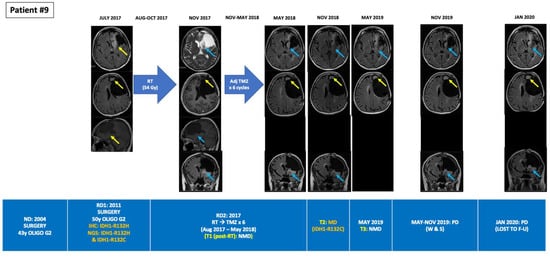

Figure 3.

Tumour evolution in BEAMing ctDNA-positive patient #9. A 58-year-old woman was diagnosed in 2004 of a grade II oligodendrogliomas undergoing a gross total resection. In 2011 the tumor relapsed, undergoing a subtotal resection with aphasia as a postsurgical sequel. The patient then received adjuvant TMZ for 12 cycles. RT was disregarded due to the potential sequelae given the large volume to irradiate. In July 2017, the patient suffered an unresectable relapse. NGS analysis of the 2011 archived tumor sample unveiled two co-existing mutations in IDH1 (R132H and R132C). RT (54 Gy in 30 fractions) was administered between August and October 2017. BEAMing plasma ctDNA analysis did not detect any mutation prior to RT. After RT the patient received adjuvant TMZ for 6 cycles. Partial response was observed after RT, but progressive disease occurred in the antero-medial surgical cavity margin from May 2018 until January 2020, when the patient was lost to follow up. In May 2018, after finishing adjuvant TMZ, BEAMing plasma ctDNA analysis detected one of the IDH1 mutations detected in the tumor resected in 2011 (ctDNA IDH1-R132C VAF 0.025%, which is above de LOD for BEAMing (>0.02%)). However, ctDNA analysis performed in November 2018 did not detect any mutation. BEAMing: Beads, Emulsion, Amplification and Magnetics, ctDNA: circulating tumor DNA, F-U: follow-up, IDH1: isocitrate dehydrogenase type 1, IHC: immunohistochemistry, LMD: leptomeningeal disease, LOD: limit of detection, MUT: mutant, NGS: next-generation sequencing, NMD: no mutation detected, pRT: palliative radiotherapy, RT: radiotherapy, SX: surgery, TMZ: temozolomide, Unmet: unmethylated, VAF: variant allele frequency.